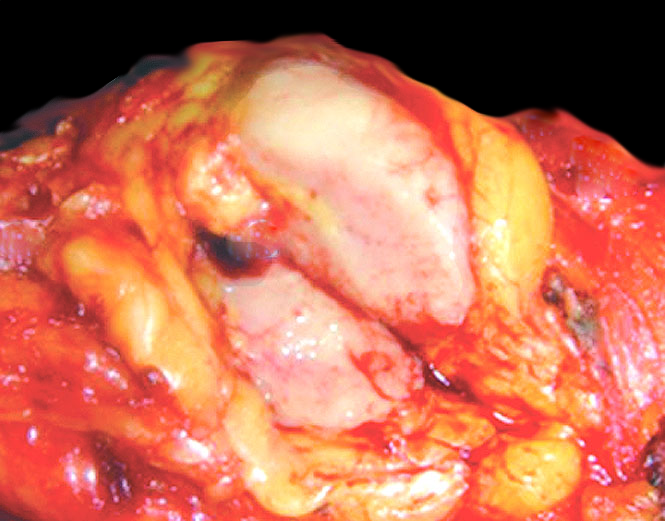

Gross description

- Ill defined firm mass (Am J Surg Pathol 2000;24:1231)

- Tan or fleshy cut surface

- Calcification, hemorrhage and necrosis uncommon